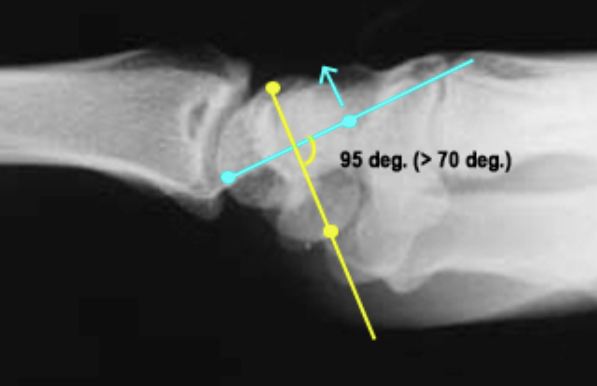

Lateral